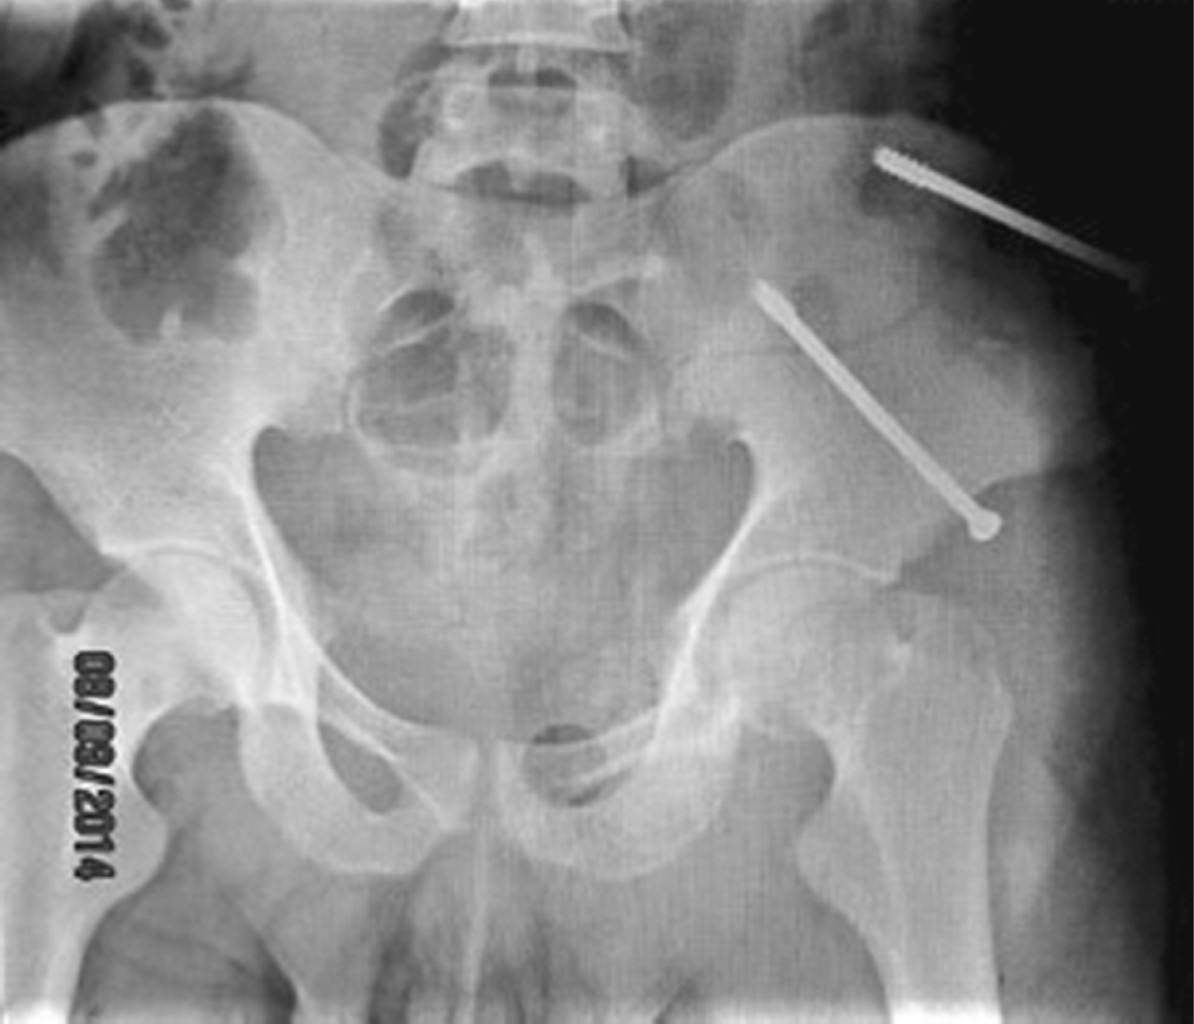

La cirugía percutánea realizada en fracturas de pelvis y acetábulo en el Hospital de Traumatología "Dr. Victorio de la Fuente Narváez", de la UMAE Magdalena de las Salinas, ha aumentado en los últimos años debido a una mayor incidencia de este patrón de lesiones que requieren un manejo alternativo a la intervención abierta de pelvis y acetábulo. En el presente estudio, se encontró que la fractura más frecuente a la que se le practicó cirugía percutánea fue la fractura tipo AO 61B2 (38.1%) (Figura 7), por otro lado, las fracturas por compresión lateral (AO 61B1, 61B2, 61B3) fue el mayor grupo al que se le efectuó tal procedimiento con 56.74%. El segundo ejemplo de fractura más usual fue la fractura de pelvis asociada con fractura de acetábulo (13.4%). En relación con las fracturas de acetábulo puro a los que se les practicó este tipo de método (Figura 8), se encontró que la fractura más habitualmente sometida a dicho procedimiento fueron las fracturas AO 62A3 (4.6%). Qoreishi y cols.9 en un artículo de cirugía percutánea, similar al aquí presentado, usan la clasificación de Young-Burgess y mencionan que el tipo de fractura más frecuente al que ellos realizaron la operación percutánea fue la fractura con mecanismo de compresión lateral con 28.7%, seguido por fracturas aisladas de acetábulo con 21.7%. De éstas, la más común fue la fractura transversa, posteriormente las fracturas de pelvis con compresión anteroposterior combinada con acetábulo con 20.3%.

Figura 7

Figura 8